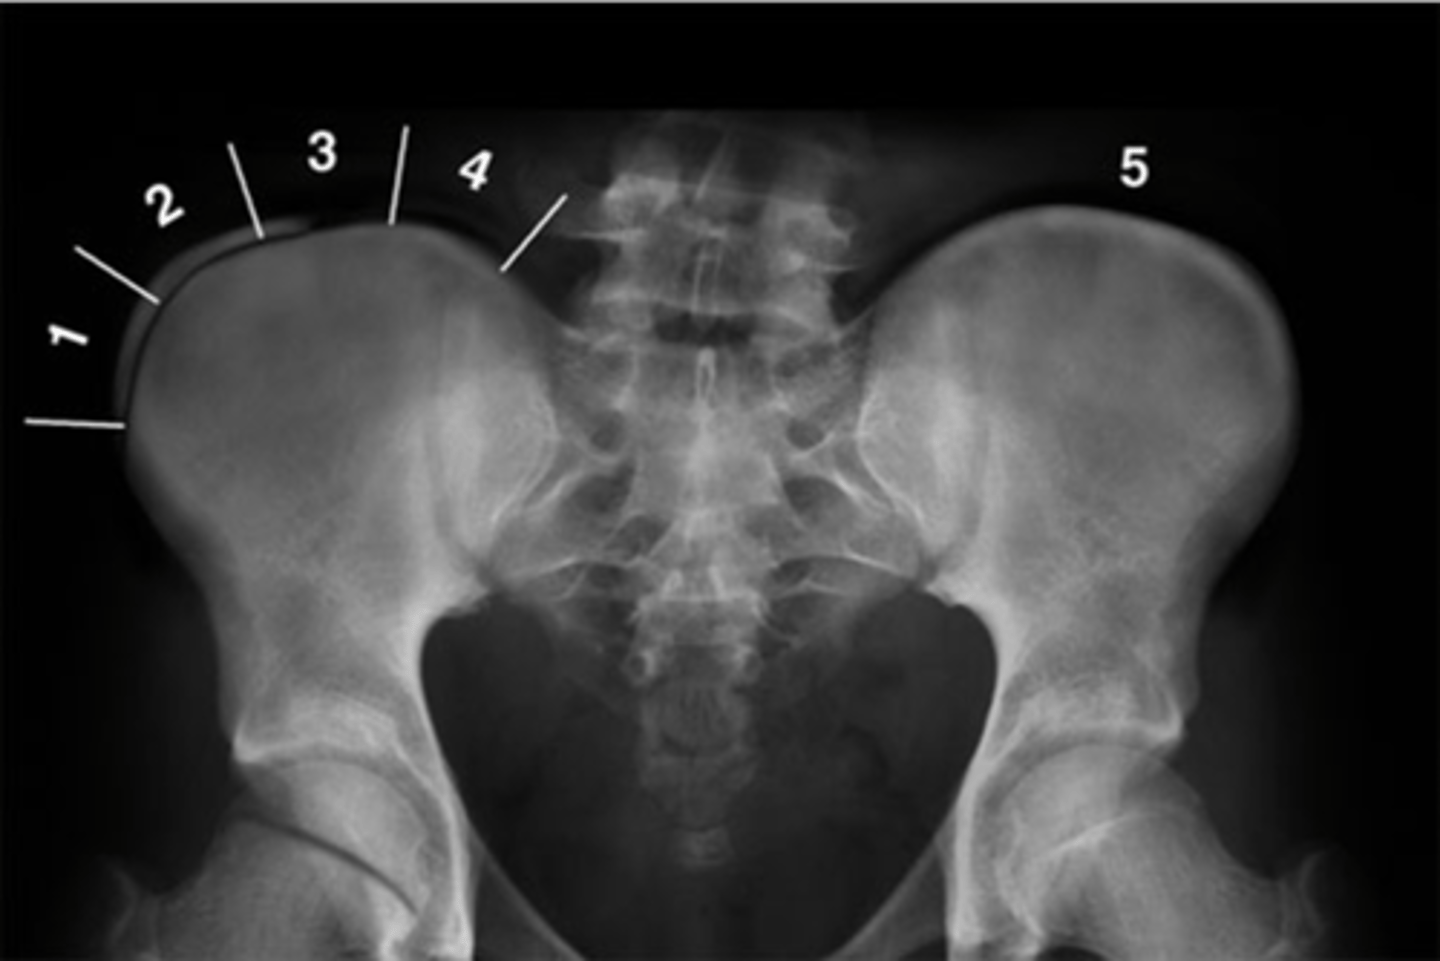

Pubic symphysis

ID 1

<p>ID 1</p>

Left femoroacetabular joint

ID 2 (joint)

<p>ID 2 (joint)</p>

Left posterior sacroiliac joint

ID 3 (joint)

<p>ID 3 (joint)</p>

Left anterior sacroiliac joint

ID 4 (joint)

<p>ID 4 (joint)</p>

Right: gluteus medius

Left: gluteal fat stripe

ID 5

<p>ID 5</p>